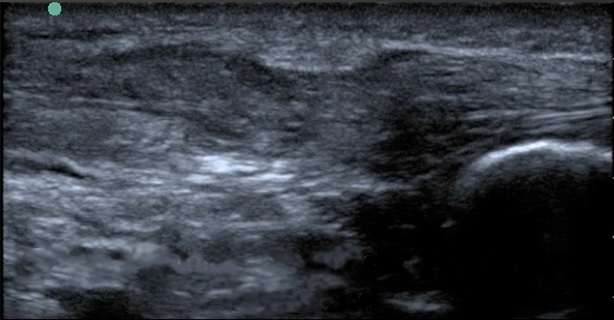

Bild: Fuß und Sprunggelenk, vollständige Ruptur der Achillessehne